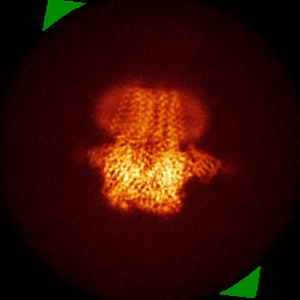

Cryo-EM structure of human full-length beta3delta GABA(A)R in complex with histamine and nanobody Nb25

Single-particle3.1 Å

Sample: Human full-length beta3delta GABA(A)R in complex with histamine and nanobody Nb25

Fitted models: 7qn8